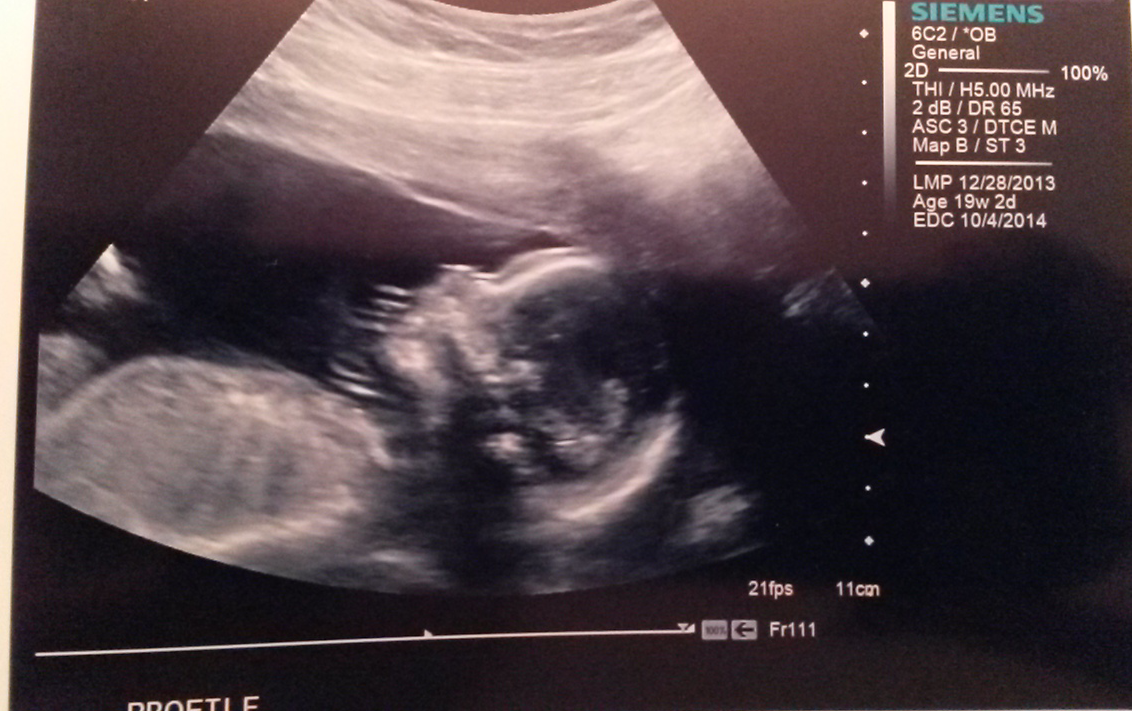

Asking for some good thoughts and vibes today! Unfortunately I have to wait until 5:15pm for our anatomy scan. I'm a ball of emotions over here. Just hoping all is well with baby. Granted, we won't find out the sex until Saturday, but I painted my nails for the occasion anyway. T&Ps welcome!

UPDATE: Well, as far as I can tell the appointment went well. The tech couldn't tell us anything because the doctor has to see the report first. But we counted fingers and toes, and I saw 4 chambers in the little heart, and the spine looked straight as far as I could tell! I did find out I have an anterior placenta, so it'll be a few more weeks until I can feel baby. We had the tech put the sex in an envelope and we packing taped it shut and it's hanging on our refrigerator to taunt us all week! C'mon, Saturday!!